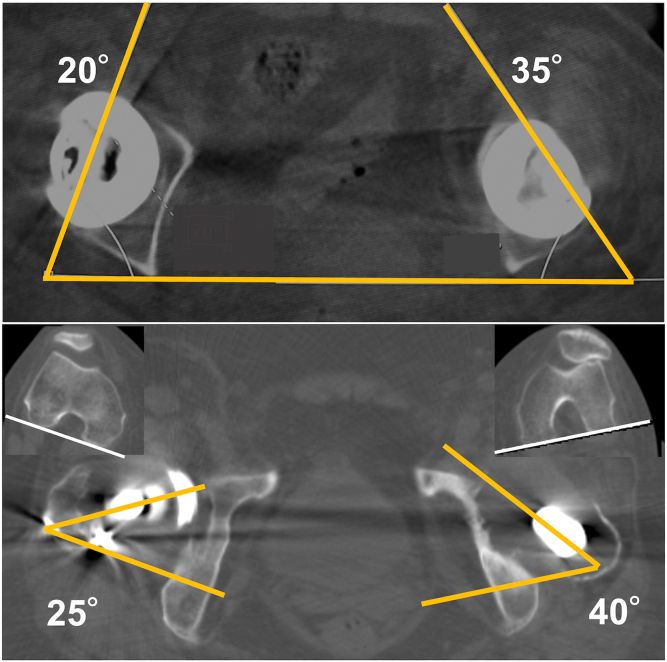

Figure 2.

Computed tomography (CT) images showing the combined anteversion angles of 75° (stem: 40° and cup: 35°) and 45° (stem: 25° and cup: 20°) in the left and right hips, respectively.

A 54-year-old female patient underwent a primary THA at an outside institution for the diagnosis of secondary osteoarthritis in the left hip. The third-generation alumina CoC bearing with a diameter of 28 mm was implanted with a self-locking TriAD HA acetabular cup and Super Secur-Fit HA femoral stem. All these implants were from Stryker (Mahwah, NJ). A right primary CoC THA using the same implant devices was performed for secondary osteoarthritis at 5 years after the left primary THA. Osteolytic lesions were found in the proximal regions of the stem (Gruen zones 1 and 7 [16]) and around the cup (DeLee and Charnley zone 3 [17]) in an anteroposterior radiograph taken at 6-year follow-up after the left primary THA (Fig. 1a). The previous study suggested a desirable combined anteversion within a range of 25°–50° [18]. A high combined anteversion angle of 75° (stem: 40° and cup: 35°) was noted in the left hip by computed tomography imaging (Fig. 2). In contrast, the combined anteversion on the right hip was within the ideal range (45°; stem: 25° and cup: 20°). A radiological sign of cup loosening was found with a progressive osteolytic lesion (Fig. 1b). Metal artifact reduction sequence magnetic resonance imaging identified a 42 × 40 × 64-mm soft-tissue mass around the femoral neck (Fig. 3) that had been asymptomatic for several years. The patient experienced mild pain in her left hip at 10 years postoperatively and was referred to our institution because of aggravated pain and the need for revision THA using allogeneic bone grafting for treating the large bone defect associated with periprosthetic massive osteolysis formation (Fig. 4).

In our patient, the cause of the periarticular mass was not apparent. There was no clear evidence of gross metal staining of the tissues, metal corrosion, and ceramic/metal wear particles on the pathological images. Also, skin patch testing gave negative results. However, the patient had a documented history of contact allergy to metal jewelry, and histopathological findings of the periarticular mass showed an ALVAL score of 8 points, with T-lymphocyte–dominant infiltration. Further immunohistochemical staining clearly indicates a predominant infiltration of Th17 cells suggestive of a hypersensitivity reaction to metal particles (Fig. 6). The impingement scars on the femoral neck and acetabular rim (Fig. 5) provide direct evidence of metal particle release from titanium alloy (Ti-6Al-4V) components, potentially promoting Th17 cell infiltration. The occurrence of hypersensitivity reactions was previously suggested to be independent of the amount of particulate wear debris due to the possibility of an idiosyncratic response to metal [31]. In line with this, it is reasonable to assume that the development of periarticular mass and osteolysis in our patient may be responsible at least in part for the hypersensitivity reaction to metal (probably, titanium) released by neck-rim impingement. This is further supported by the absence of ALTR in the contralateral CoC THA with the ideal implant position (Fig. 2). Therefore, it is necessary to keep in mind the risk of ALTR as well as ceramic wear and fracture in CoC THA, and patient background such as metal allergic conditions should be carefully considered. Furthermore, accurate component placement is an important factor in avoiding impingement and edge loading, which can be a source of metal particles.